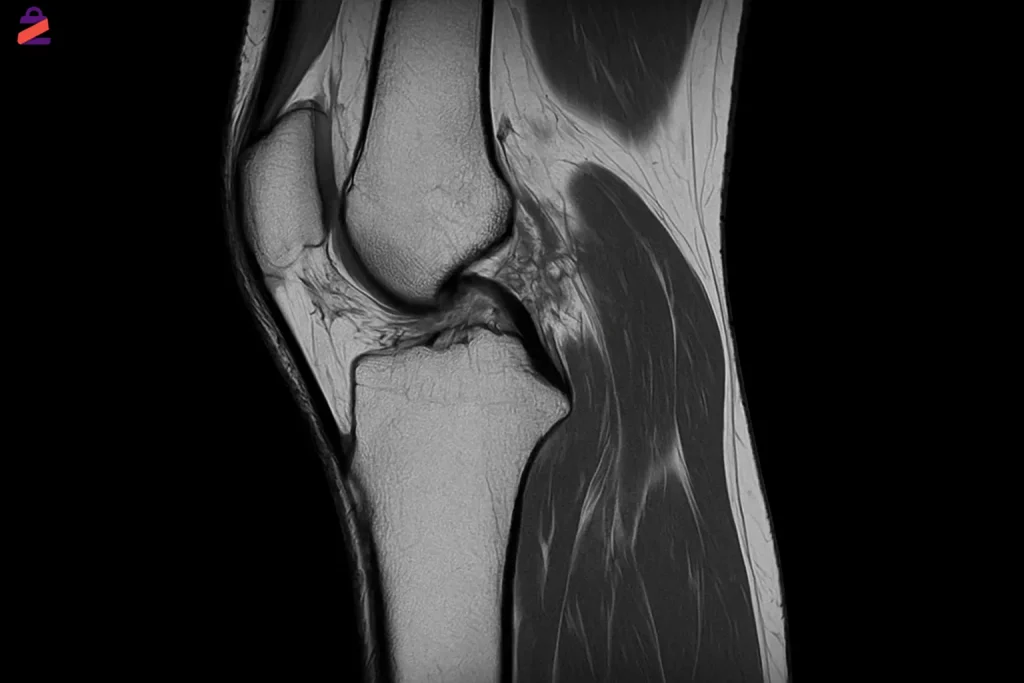

ام آر آی زانو یک روش تصویربرداری پیشرفته و غیرتهاجمی است که برای بررسی دقیق بافتهای داخلی مفصل زانو مانند رباطها، غضروفها، مینیسکها، استخوان و سایر بافتهای نرم استفاده میشود. این روش با استفاده از میدان مغناطیسی قوی و امواج رادیویی، تصاویر بسیار واضح و چندبُعدی تولید میکند که به پزشک در تشخیص دقیق آسیب یا بیماری کمک میکند—بدون نیاز به اشعه ایکس یا جراحی.

تصویربرداری MRI زانو امکان مشاهدهی دقیق ساختارهای مختلف درون مفصل زانو را فراهم میکند، بهویژه آن دسته از اجزایی که با روشهایی مانند رادیولوژی قابل مشاهده نیستند. این تکنولوژی پیشرفته برای بررسی کامل بافتهای نرم، اجزای غضروفی، استخوانی و حتی مایعات مفصلی به کار میرود و کمک میکند تا کوچکترین آسیبها یا اختلالات عملکردی شناسایی شوند. به همین دلیل، ام آر آی ابزاری حیاتی در تشخیص دقیق و برنامهریزی درمانی بهشمار میرود. اجزای قابل بررسی به وسیله ام آر آی زانو عبارتند از:

- مینیسک داخلی و خارجی (پارگی، تحلیل یا جابجایی)

- رباطهای زانو شامل ACL، PCL، MCL و LCL

- غضروف مفصلی (ساییدگی یا ترکخوردگی)

- استخوان ران، ساق و کشکک (ضایعات استخوانی یا التهاب مغز استخوان)

- تاندونها و عضلات اطراف زانو

- بورساها و کیسههای مفصلی (بررسی التهاب یا پرشدگی)

- مایع مفصلی و بافتهای سینوویال (در تشخیص آرتریت یا عفونت)